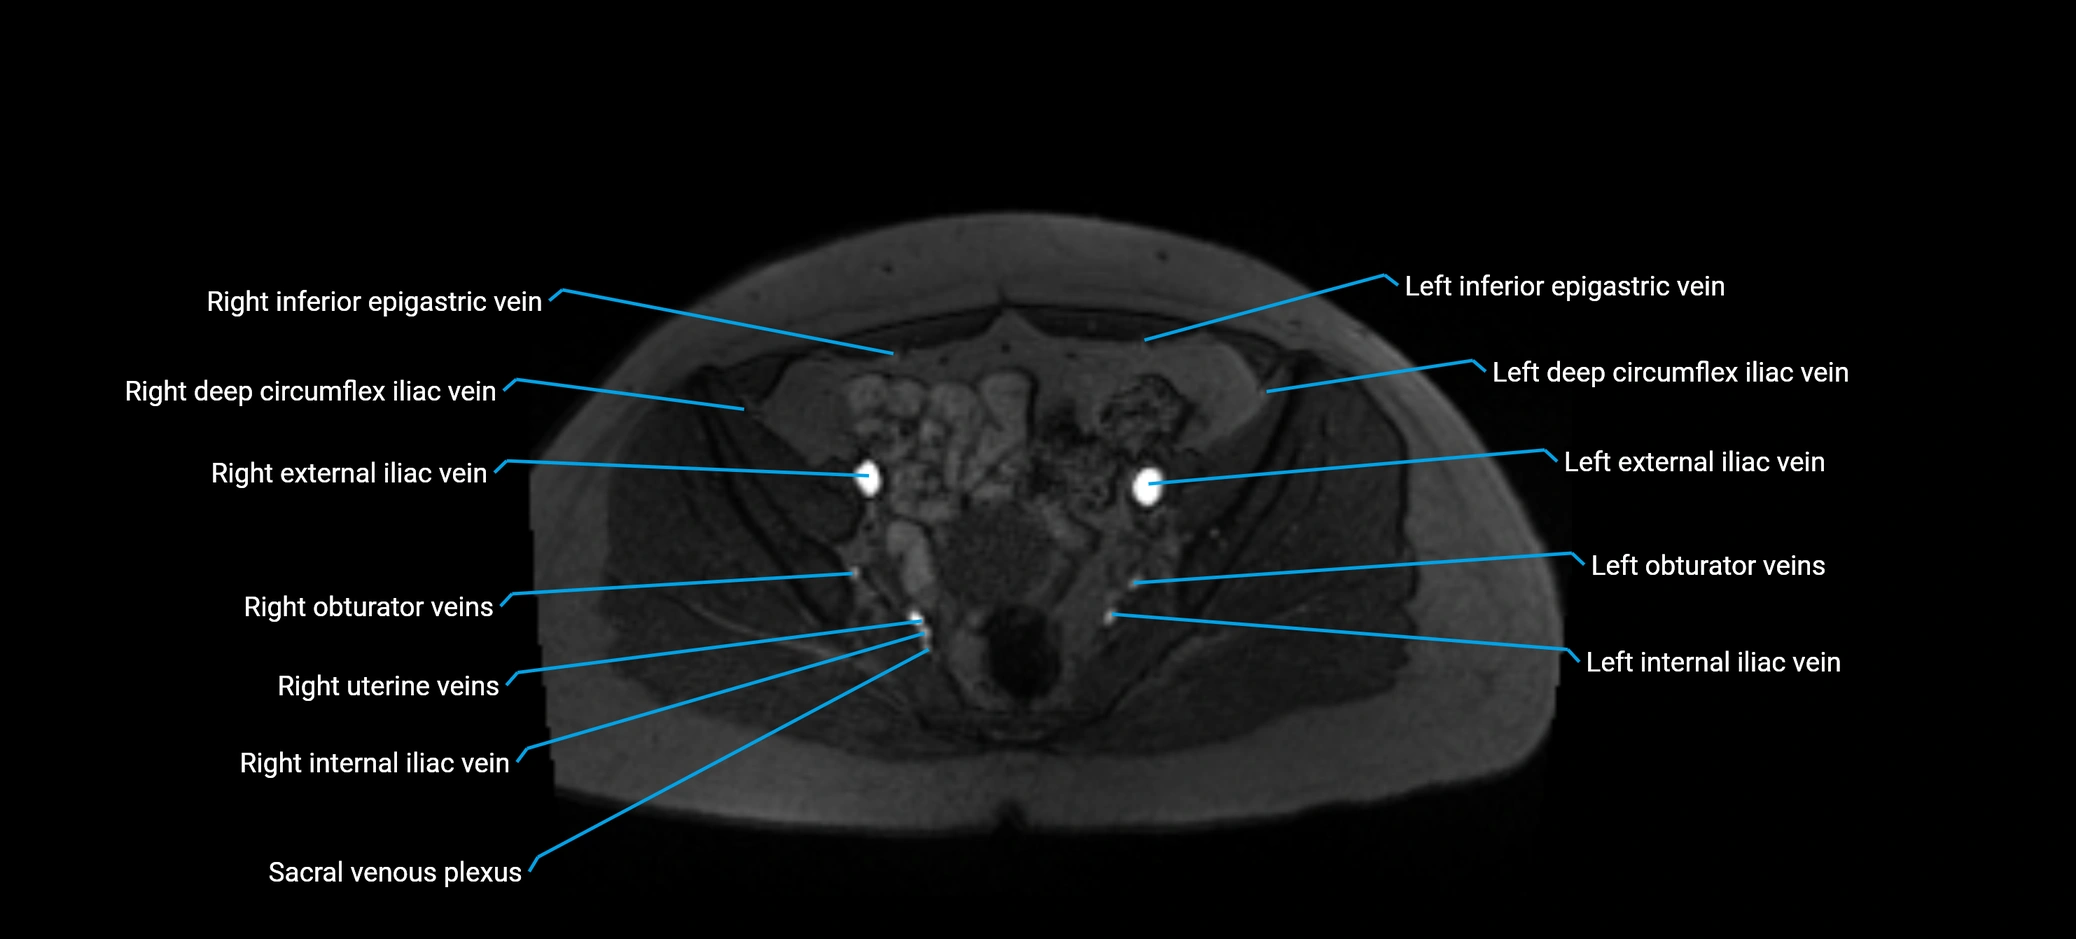

MRI image

image